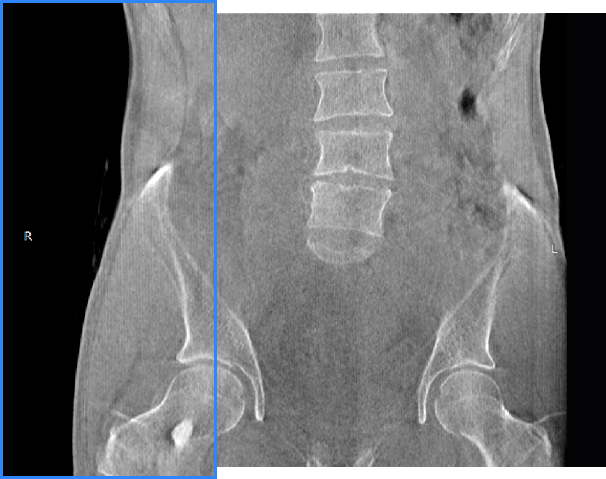

髖關節

FOV 250mm

FOV 350mm